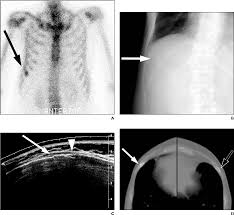

Actually, breast cancer would only cause pain in the ribs as well as tenderness when it has actually spread to the bones, this is a very late stage of cancer and usually, this would not be the first symptom of breast cancer. I was wrongly diagnosed with costochondritis (inflamed cartilage around the ribs) for eighteen months. Limbs (upper arm and upper leg bones) pelvis (hipbones) rib cage. Any type of breast pain can be very distressing, and many women worry they may have breast cancer. Chest wall pain can cause a sharp, stabbing pain. Many people receive effective treatment at this stage and do not develop other. This was followed by left kidney pain which left me shivering, urgency to urinate and extreme thirst and generally feeling unwell. The bones most commonly affected are the: A bone scan (that i eventually insisted on) revealed that i had widespread bone mets. One of the symptoms of lung cancer is rib cage pain or chest pain that gets worse upon breathing deeply, coughing, or laughing. A nagging pain under the right ribcage that won't go away can be a symptom of cancer; Pain in the rib cage can be sharp, dull or achy, and it can be felt at or below the chest or above the naval on either side, explains healthline. Women may feel discomfort and pain as the cancer grows and spreads in the breast.

The tumor in the breast: Unfortunately, breast cancer can recur in the ribs or the chest wall. It is an early stage of breast cancer, meaning the tumor is often very small. Chronic pain experienced in the ribs can be a sign of bone cancer, according to healthline. Limbs (upper arm and upper leg bones) pelvis (hipbones) rib cage. Thickening or lump in breast or other parts of the body: The bone is the most common site of secondary breast cancer. A bone scan (that i eventually insisted on) revealed that i had widespread bone mets. Other symptoms include wheezing, shortness of breath, and coughing up phlegm or blood. With this type of cancer, the area of skin over the tumor can. Back pain can be a symptom of metastatic breast cancer because when this disease spreads, it often goes to bone, benjamin smith, m.d., an associate professor of radiation oncology at md anderson. Do not take a diagnosis of muscle pull as the gospel if that tiny voice inside of you isn't quite agreeing with this. Pain in the rib cage can be sharp, dull or achy, and it can be felt at or below the chest or above the naval on either side, explains healthline.

Breast Cancer Overview Cancer Council Victoria from www.cancervic.org.au Metastatic breast cancer can involve back pain. Other symptoms include wheezing, shortness of breath, and coughing up phlegm or blood. Before this symptom actually occurs, a patient would invariably experience a lump in the breast or changes in the skin of. Secondary breast cancer in the bone is not the same as having cancer that starts in the bone. This pain worsens from coughing, deep breathing, or even laughing. With this type of cancer, the area of skin over the tumor can. Women may feel discomfort and pain as the cancer grows and spreads in the breast. A doctor should be consulted to properly diagnose the condition with a bone scan.